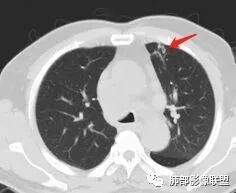

但是有一个地方有问题的,左侧的上叶的下舌段这个区域:

左上叶舌段这个气管腔内是有东西凸进去。

首先弥漫性的,支气管壁是一个问题,然后有病灶凸向腔内,那又是一个问题,我有两种想法。

1、支气管壁本身有问题,2周围淋巴结侵犯支气管壁